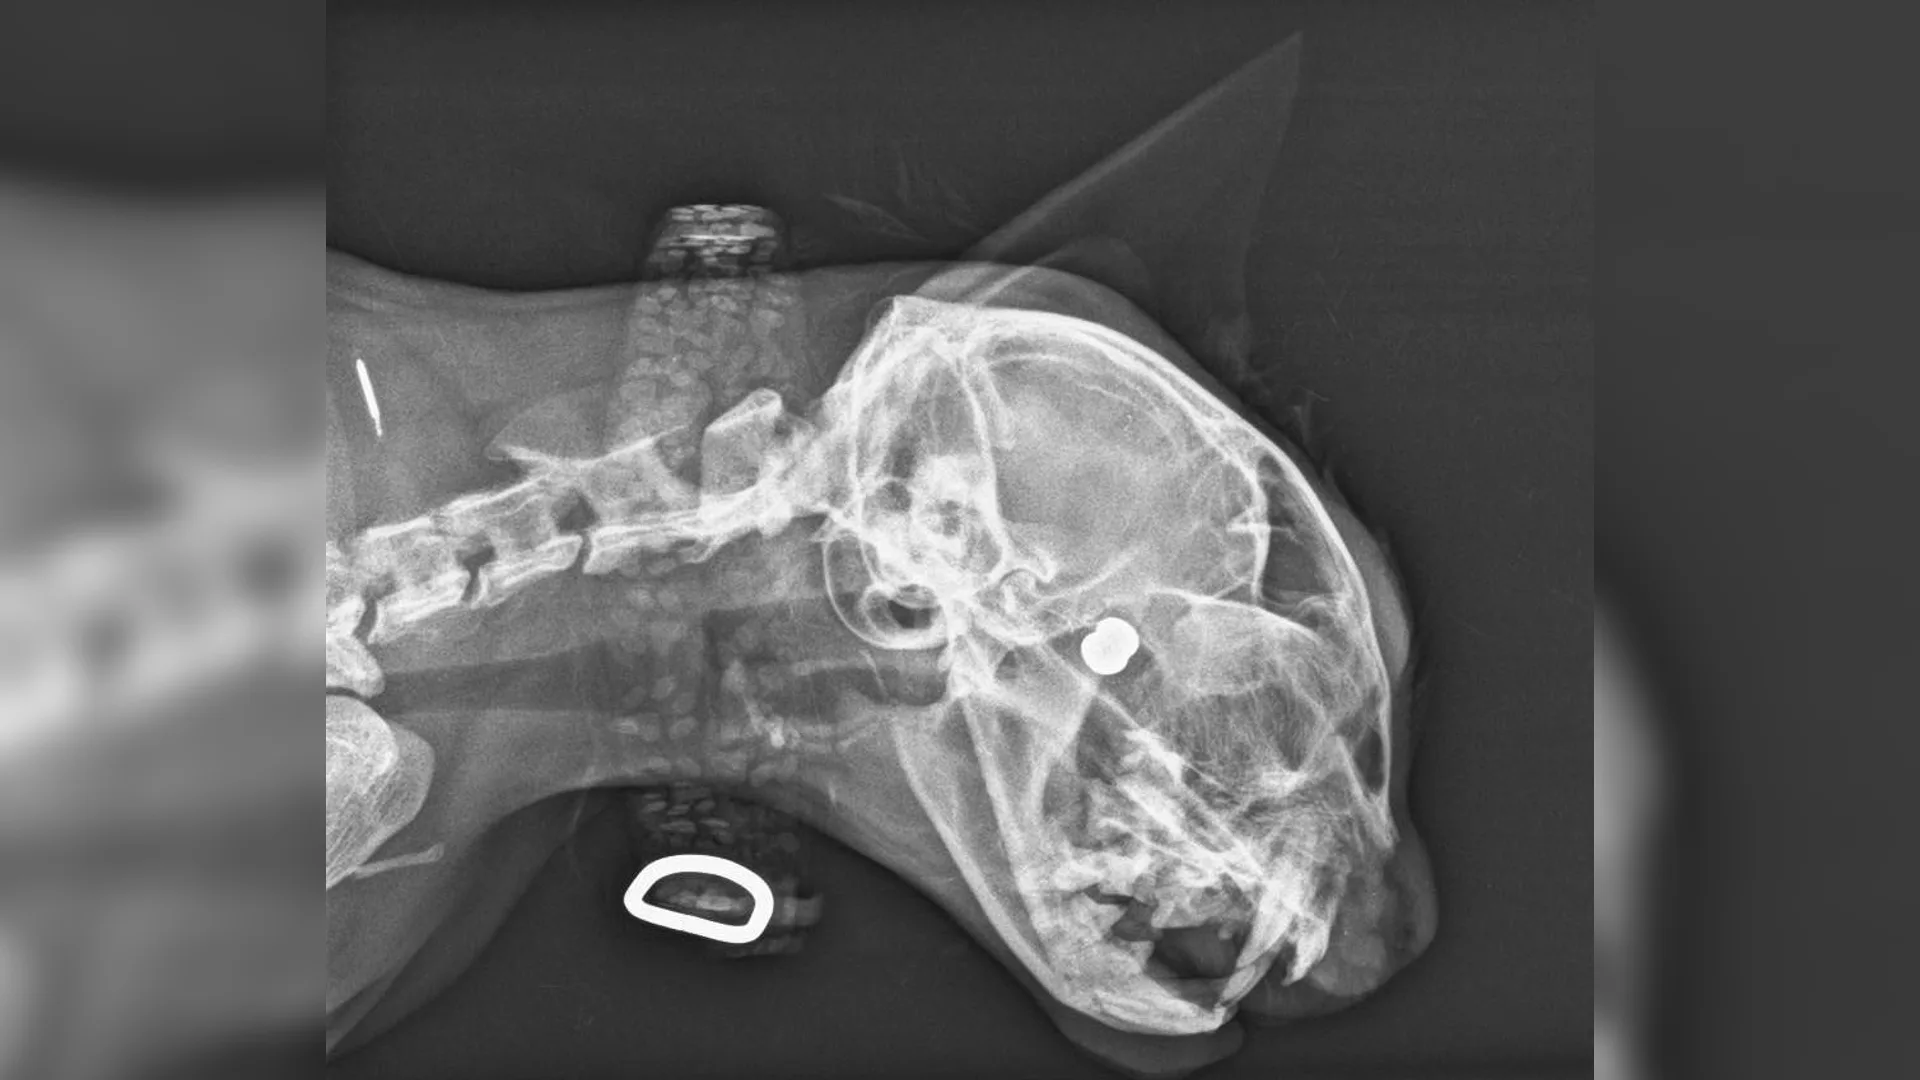

De kat die maandag gewond raakte nadat hij was beschoten in Soest, is helaas overleden. Dat meldt de politie op Facebook. De dierenarts heeft het dier moeten laten inslapen.

De kat is waarschijnlijk beschoten door iemand met een luchtbuks, meldde de politie eerder. Het dier was al zes dagen vermist uit de omgeving van de Hofstedering toen het uiteindelijk zaterdagochtend met een gat in zijn kopje thuis kwam.